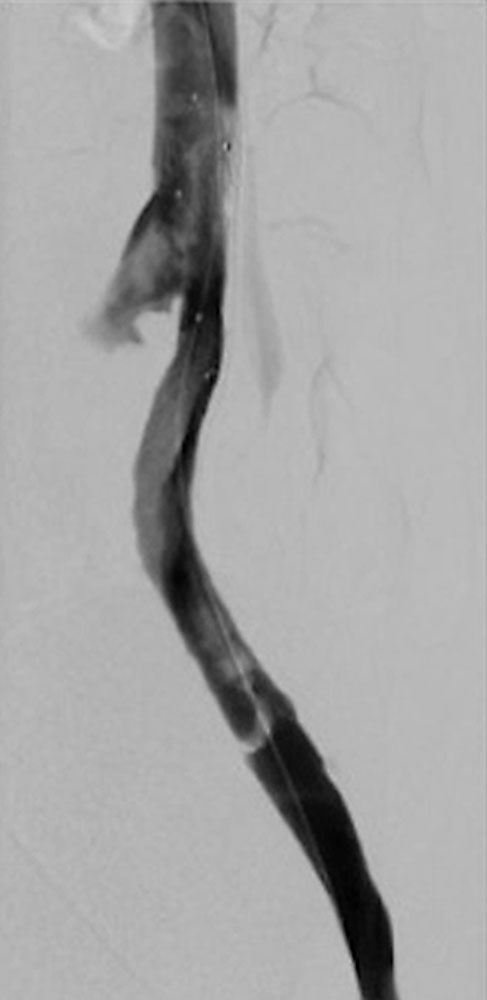

Invasive measures today often include minimally invasive, catheter-guided mechanical or pharmacomechanical procedures. In these procedures, the acute thrombus is dissolved by mechanical or pharmacomechanical catheter therapy in a minimally invasive manner. Chronic occlusion, especially in the iliofemoral location descending from an iliac vein, can also be reopened minimally invasively, and stents are usually implanted. Open surgical therapy of acute thrombosis is very rarely indicated today, primarily in cases of iliofemoral thrombosis with occlusion of the pelvic venous circulation, and may be combined with creation of an arteriovenous fistula in the groin to keep the reopened vein open. However, appropriate measures should always be performed at a center.

Specific therapeutic measures for phlebothrombosis in patients with venous malformations (VM) should be performed if the vascular malformation is the cause of the thrombosis. This is usually the case in large venous malformations that have one or more communicating veins from the VM into the draining venous system (also called “drainage vein”), and in VM patients with large, dysplastic, dilated veins that communicate with the conducting deep venous system (e.g., marginal veins in patients with Klippel-Trénaunay syndrome) or an embryonically persistent sciatic vein in the thigh. In these cases, occlusion of these communicating veins by minimally invasive or open surgical measures should be performed as causal therapy to avoid thromboembolism with pulmonary embolism in the long run.

Targeted occlusion of large, dysplastic veins or communicating veins from a venous malformation can prevent recurrence of thrombosis causally.